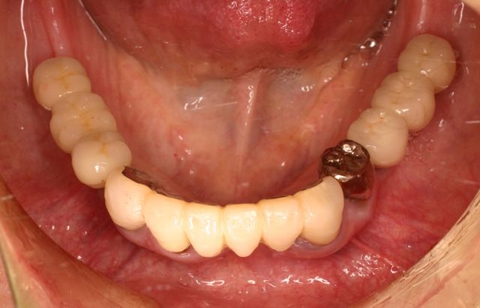

両側5歯症例

両側5歯症例両側5歯症例両側5歯症例 主訴-義歯のバネが壊れて手前の歯が痛んできた。 術前(旧義歯装着、鏡像) 術前(下顎粘膜面、鏡像)術前(下顎粘膜面、鏡像)術前(下顎粘膜面、鏡像) 術前レントゲン術前レントゲン術前レントゲン 術前口腔内(正面観)術前口腔内(正面観)術前口腔内(正面観)

術後(鏡像)術後(鏡像)術後(鏡像) 術後口腔内(正面観)術後口腔内(正面観)術後口腔内(正面観)もう入れ歯は要らなくなりました。 術後レントゲン術後レントゲン術後レントゲン